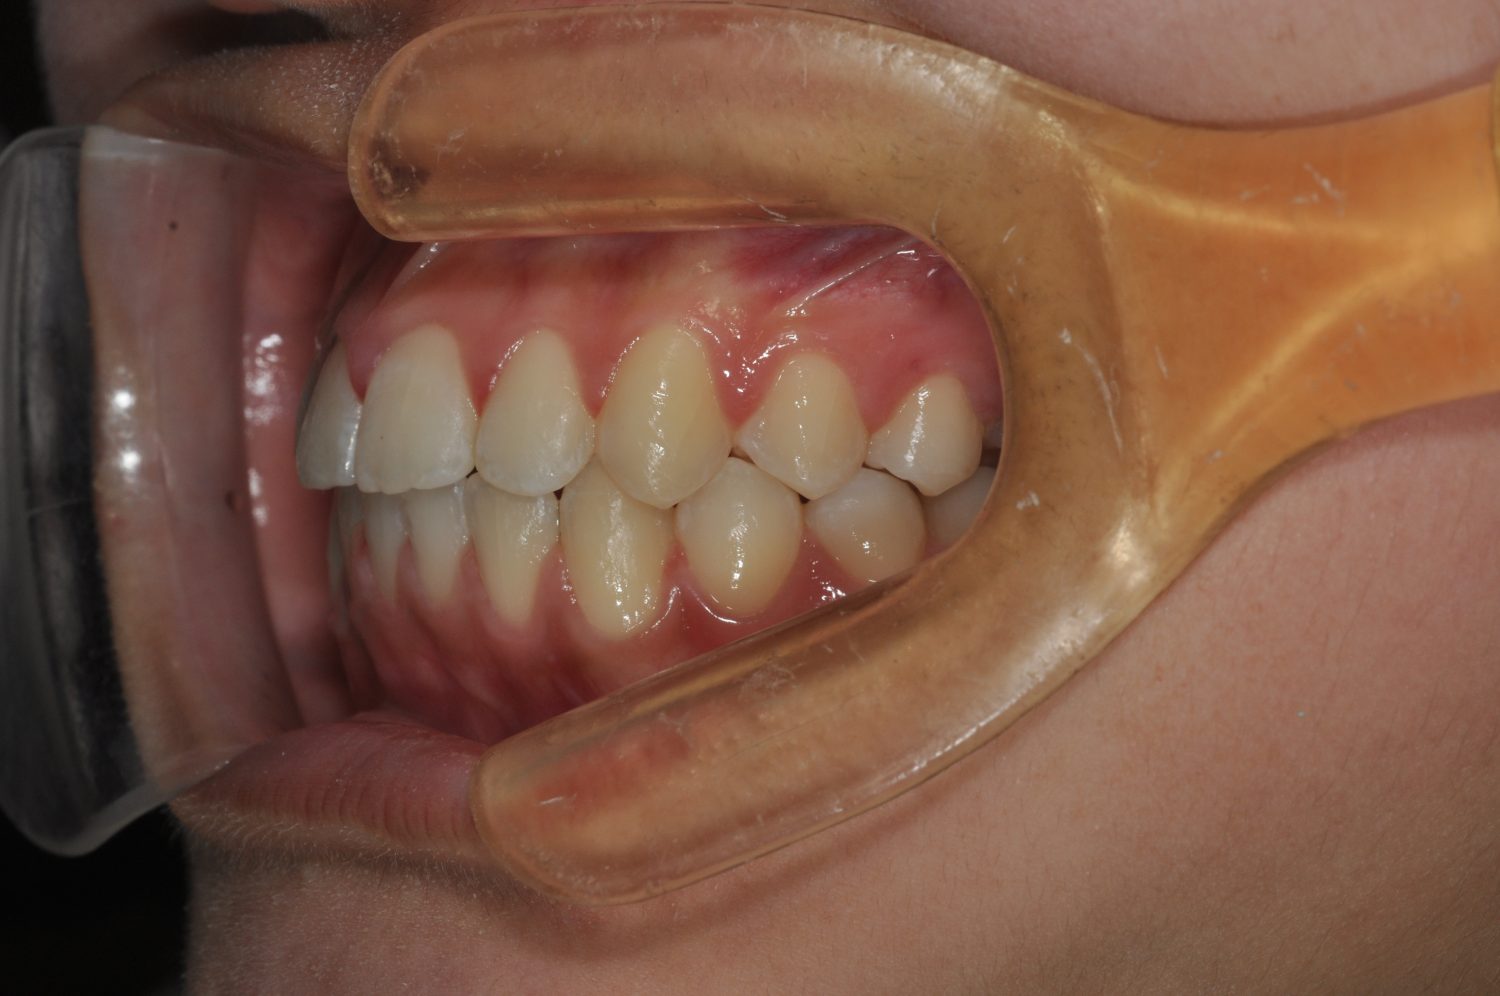

| 主訴 | 口唇の突出感 |

| 治療内容 | 小臼歯抜歯によるマルチブラケット治療 |

| 治療期間 | 1年7ヶ月 |

| 想定されたリスク | 矯正後、後戻りする可能性がありました。また、歯根吸収や歯肉退縮のリスクがありました。 |